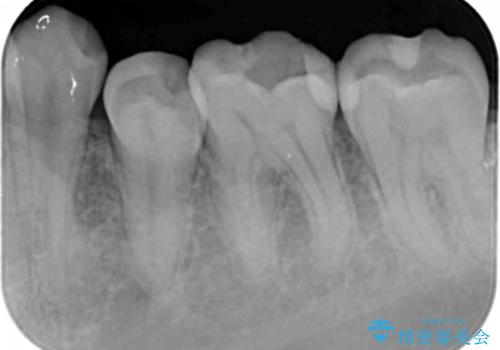

- 左下に詰めた樹脂の変色を主訴に来院されました。

同じ樹脂の材料で詰め直しをしたところでまた変色してしまうリスクが高いため、セラミックでの治療となりました。